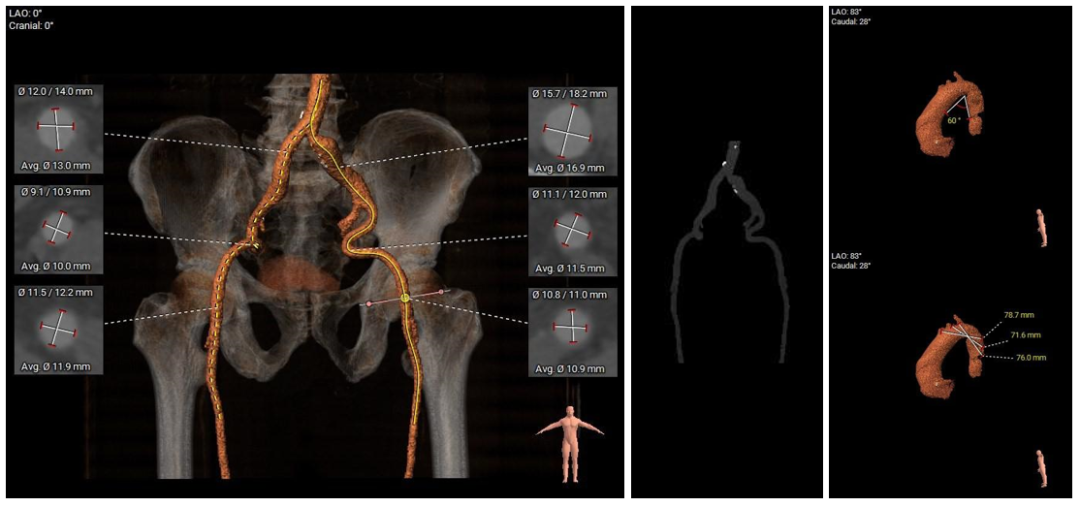

术前CT评估

• Type1型二叶式主动脉瓣,L-R间可见钙化融合脊,瓣叶增厚伴中度钙化,钙化主要分布于左冠瓣叶边缘及左无交界处,左室流出道呈敞口型;

• 左右冠开口高度尚可,切线位测量未见冗长瓣叶;冠脉未见钙化斑块;

• 瓦氏窦、窦管交界内径尚可,升主动脉扩张;左室腔内径偏大,心室壁厚度尚可;

• 瓣环水平夹角为61°,主动脉弓距及弓部夹角偏小;降主动脉扭曲折叠成角;

• 双侧股髂动脉轻度扭曲,左髂总动脉局部扩张,主动脉弓、腹主动脉下段、左侧髂总动脉可见散在钙化斑块,股动脉穿刺处未见钙化斑块;入路血管直径良好。

主动脉根部测量

瓣上结构测量

冠脉阻挡风险、左室大小及横位心评估

外周血管入路评估